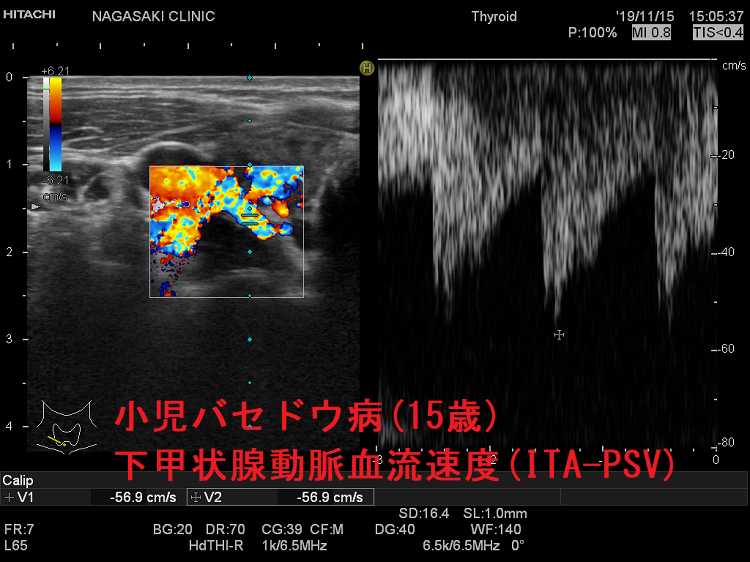

小児バセドウ病(15歳)超音波(エコー)所見は、基本的に成人と同じです。年齢ごとの正常甲状腺サイズの統一基準が無いため、比較は難です。